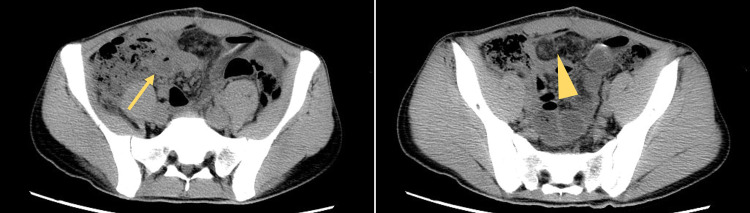

Case presentation: A 21-year-old man underwent open appendectomy after antibiotic treatment for acute appendicitis proved ineffective. Postoperative pathological findings confirmed acute appendicitis. Antibiotics were continued after surgery, and the patient's fever and abdominal symptoms gradually improved. However, abdominal distension recurred on the 18th day of hospitalization. Blood tests showed a re-elevation of the white blood cell count, suggesting a postoperative intraperitoneal abscess. Despite further antibiotic treatment, fever and leukocytosis persisted. On the 28th day of hospitalization, abnormal lymphocytes were detected in the peripheral blood, and we realized that the persistent fever was due to systemic symptoms of malignant lymphoma rather than a complication of appendicitis. On the 30th day, the patient was referred to the hematology department and subsequently diagnosed with Burkitt lymphoma. Chemotherapy was initiated on the 40th day of hospitalization. At the time of this writing, the patient had remained alive without recurrence for 4 years 3 months postoperatively.